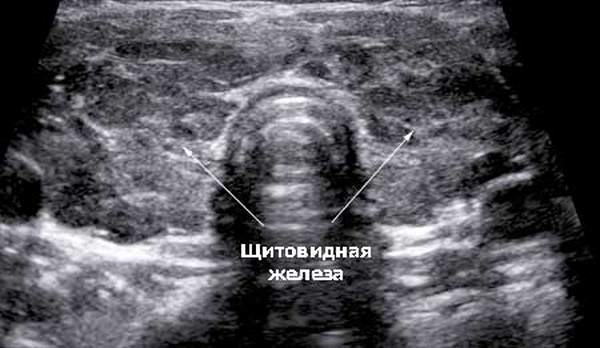

Ультразвуковое исследование органов и тканей стало важным инструментом для врачей-диагностов. Все физические тела отражают ультразвуковые волны, но степень отражения варьируется. Некоторые ткани отражают звук почти полностью, в то время как другие пропускают звуковые колебания без значительных помех. Визуализация — превращение ультразвукового сигнала в изображение на мониторе — позволяет врачу исследовать внутренние органы без введения зондов и повреждения кожи пациента. Эхогенность щитовидной железы помогает оценить её состояние и выявить заболевания на ранних, бессимптомных стадиях.

Щитовидная железа имеет рыхлую структуру, состоящую из множества пузырьков-фолликулов, заполненных белковым гелем. При прохождении ультразвука через щитовидку на мониторе появляется размытое изображение, которое демонстрирует строение и размеры органа. При патологиях изменяется плотность тканей. Например, при воспалении в фолликулах скапливается больше жидкости, что облегчает прохождение ультразвука. Если в паренхиме образуется узел, отражательная способность этого участка увеличивается, и он становится заметным на фоне здоровых фолликулов. На экране появляется изображение патологической структуры, позволяющее оценить размеры и состав клеток узла.

У здорового человека щитовидная железа имеет изоэхогенную структуру. Фолликулы одинакового размера равномерно заполнены белковым гелем и отражают ультразвуковые волны с одинаковой интенсивностью. На мониторе появляется равномерное черно-белое изображение, где щитовидка выглядит как «бабочка». Структура зернистая, цвет — равномерно серый. Врач-диагност может оценить размеры и расположение щитовидной железы и подтвердить отсутствие патологических изменений, о чем предположил врач-эндокринолог.